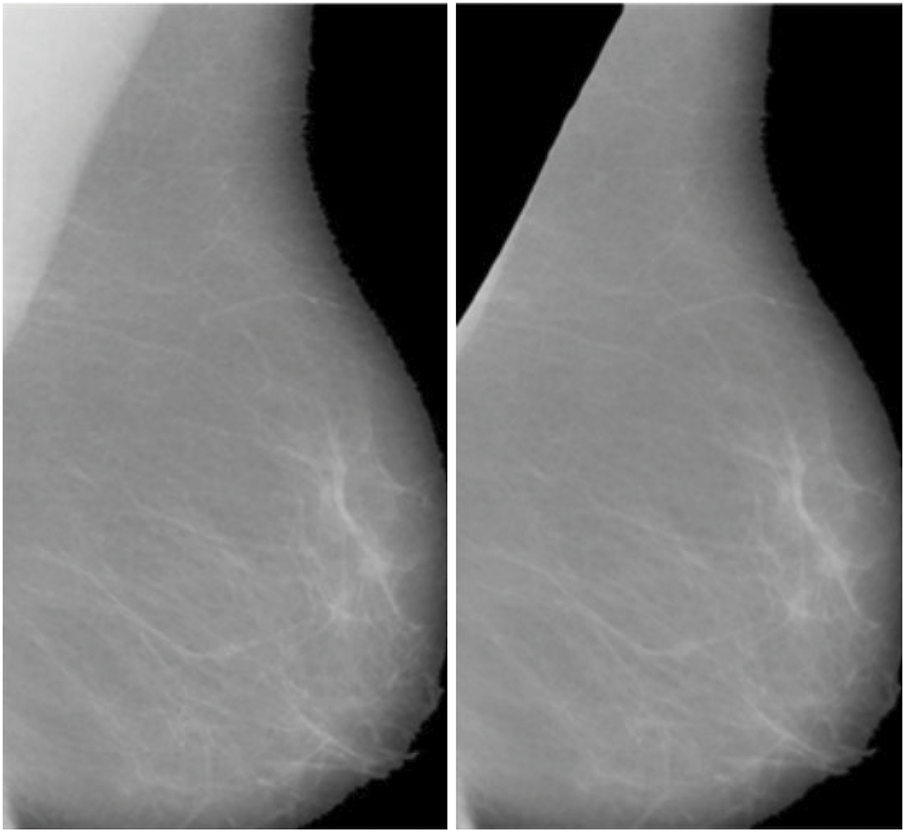

After applying Wiener filtering to reduce noise in mammographic images, the next crucial step is segmenting the breast area by removing the pectoral muscle (Fig. 3). The pectoral muscle, a bright-intensity area generally found in the upper section of MLO views, can obstruct the assessment of breast tissue, which represents the main ROI for identifying anomalies. The seed-based region-growing technique is employed for this segmentation task due to its accuracy and adaptability to the structural and intensity characteristics of mammographic images. Seed-based region growing is a widely used image segmentation method based on two key principles: selecting pixel intensity values and determining seed points. This study utilizes the seed point approach, which offers an automatic and orientation-specific selection mechanism, eliminating the need for manual intervention. By adapting to the geometric orientation of the mammographic image, the seed point approach ensures consistent and accurate initialization of the segmentation process. The segmentation process begins with the identification of a seed point, which serves as the initial position for the region expansion method. The algorithm iteratively examines the pixel intensities of neighboring pixels to determine their inclusion in the region. A pixel is added to the growing region if its intensity matches predefined similarity criteria, such as intensity threshold, gradient, or texture similarity, relative to the seed point or the existing region. This iterative process continues until the region growth stabilizes, indicating that no additional pixels meet the inclusion criteria. For mammographic images, the seed point selection is adapted to target the structural characteristics of the pectoral muscle, facilitating its isolation and removal. The algorithm effectively handles variations in intensity and orientation, ensuring robust segmentation across different images. The pectoral muscle is progressively excluded, leaving behind the breast tissue as the segmented ROI. The result of the seed-initiated region expansion procedure, as illustrated in Fig. 3, demonstrates a clean and accurate separation between the breast area and the pectoral muscle. This segmentation step is essential for reducing irrelevant regions in the image and focusing on the breast tissue, which often contains diagnostic features such as masses or microcalcifications. By isolating the breast region, the segmentation process enhances the subsequent steps of detecting abnormalities, improving the overall accuracy of computer-aided detection systems. The seed-based region-growing method also preserves the integrity of fine details and edges within the breast tissue. This capability is crucial for detecting small or early-stage abnormalities, which are often subtle and may be obscured by excessive smoothing or imprecise segmentation. Furthermore, the method’s iterative and automated approach ensures reproducibility and reliability, key factors in high-stakes diagnostic applications. This segmentation method contributes significantly to the overall diagnostic process by providing a refined ROI for further analysis. The distinct separation of the breast area aids in recognizing and classification of malignant regions, leading to improved accuracy in breast cancer detection and classification. These outcomes are further elaborated in the results section, where the effectiveness of the segmentation technique in enhancing diagnostic performance is discussed in detail.

Figure 3: Final Breast scan with partial removal of the pectoral muscle